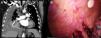

A 70-year-old man with a history of paroxysmal atrial fibrillation and COVID-19 pneumonia who required admission to the ICU for 30 days. One month later, he presented dyspnoea and orthopnoea. A lung CT (Fig. 1A) showed a predominantly right bilateral pleural effusion. Surgical evacuation was decided, given the volume of perfusion. The patient entered the operating room with severe dyspnoea and 88% oxygen saturation. General anaesthesia was performed with a 37Fr double lumen tube. The patient's blood oxygen fell during selective blockade of the right lung, but improved when the haemothorax was drained. After evacuation, multiple pleural implants forming clusters and a necrotic implant in the posterior parietal pleura were observed (Fig. 1B). This suggests that the patient had an undiagnosed tumour that had progressed rapidly during bilateral COVID-19 pneumonia.

(A) Coronal CT of pulmonary arteries showing right pleural effusion (yellow star) causing compressive atelectasis of the underlying lung (red arrow). (B) Video thoracoscopy image (VATS) showing parietal pleural tissue with implants forming clusters (yellow star) and lung (blue star). Colour images are only shown in the online version of the article.